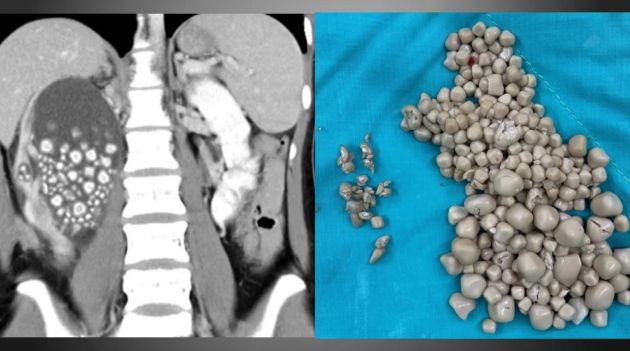

Um caso inusitado chamou a atenção de médicos em Taiwan. Os profissionais removeram mais de 300 pedras (com tamanhos variando entre 0,5 e 2 centímetros) do rim de uma jovem. A paciente disse ter deixado de beber água há vários anos.

Quando questionada sobre sua condição, ela disse aos médicos que quase não toma água. Ela contou que se hidrata com chás açucarados, suco de frutas e bebidas alcoólicas, há anos e isso resultou em desidratação crônica e acúmulo de minerais nos rins. Após exames preliminares, os médicos perceberam que o rim direito da paciente estava gravemente inchado e fizeram uma radiografia para determinar a causa. Eles ficaram surpresos ao descobrir que o órgão continha mais de 300 pedras, variando entre 0,5 e 2 centímetros.

Após um procedimento de 2 horas, chamado nefrolitotomia percutânea, os médicos removeram a enorme quantidade de pedras de seu rim, que, segundo o cirurgião-chefe, Lin Caiyang, pareciam pequeninos pães cozidos no vapor. Ela recebeu alta dias depois, segundo a imprensa da ilha asiática. Os médicos apontaram a genética, a quase total falta de ingestão de água e a dieta diária como os fatores mais importantes para a formação de cálculos renais na mulher. As informações são do UOL.